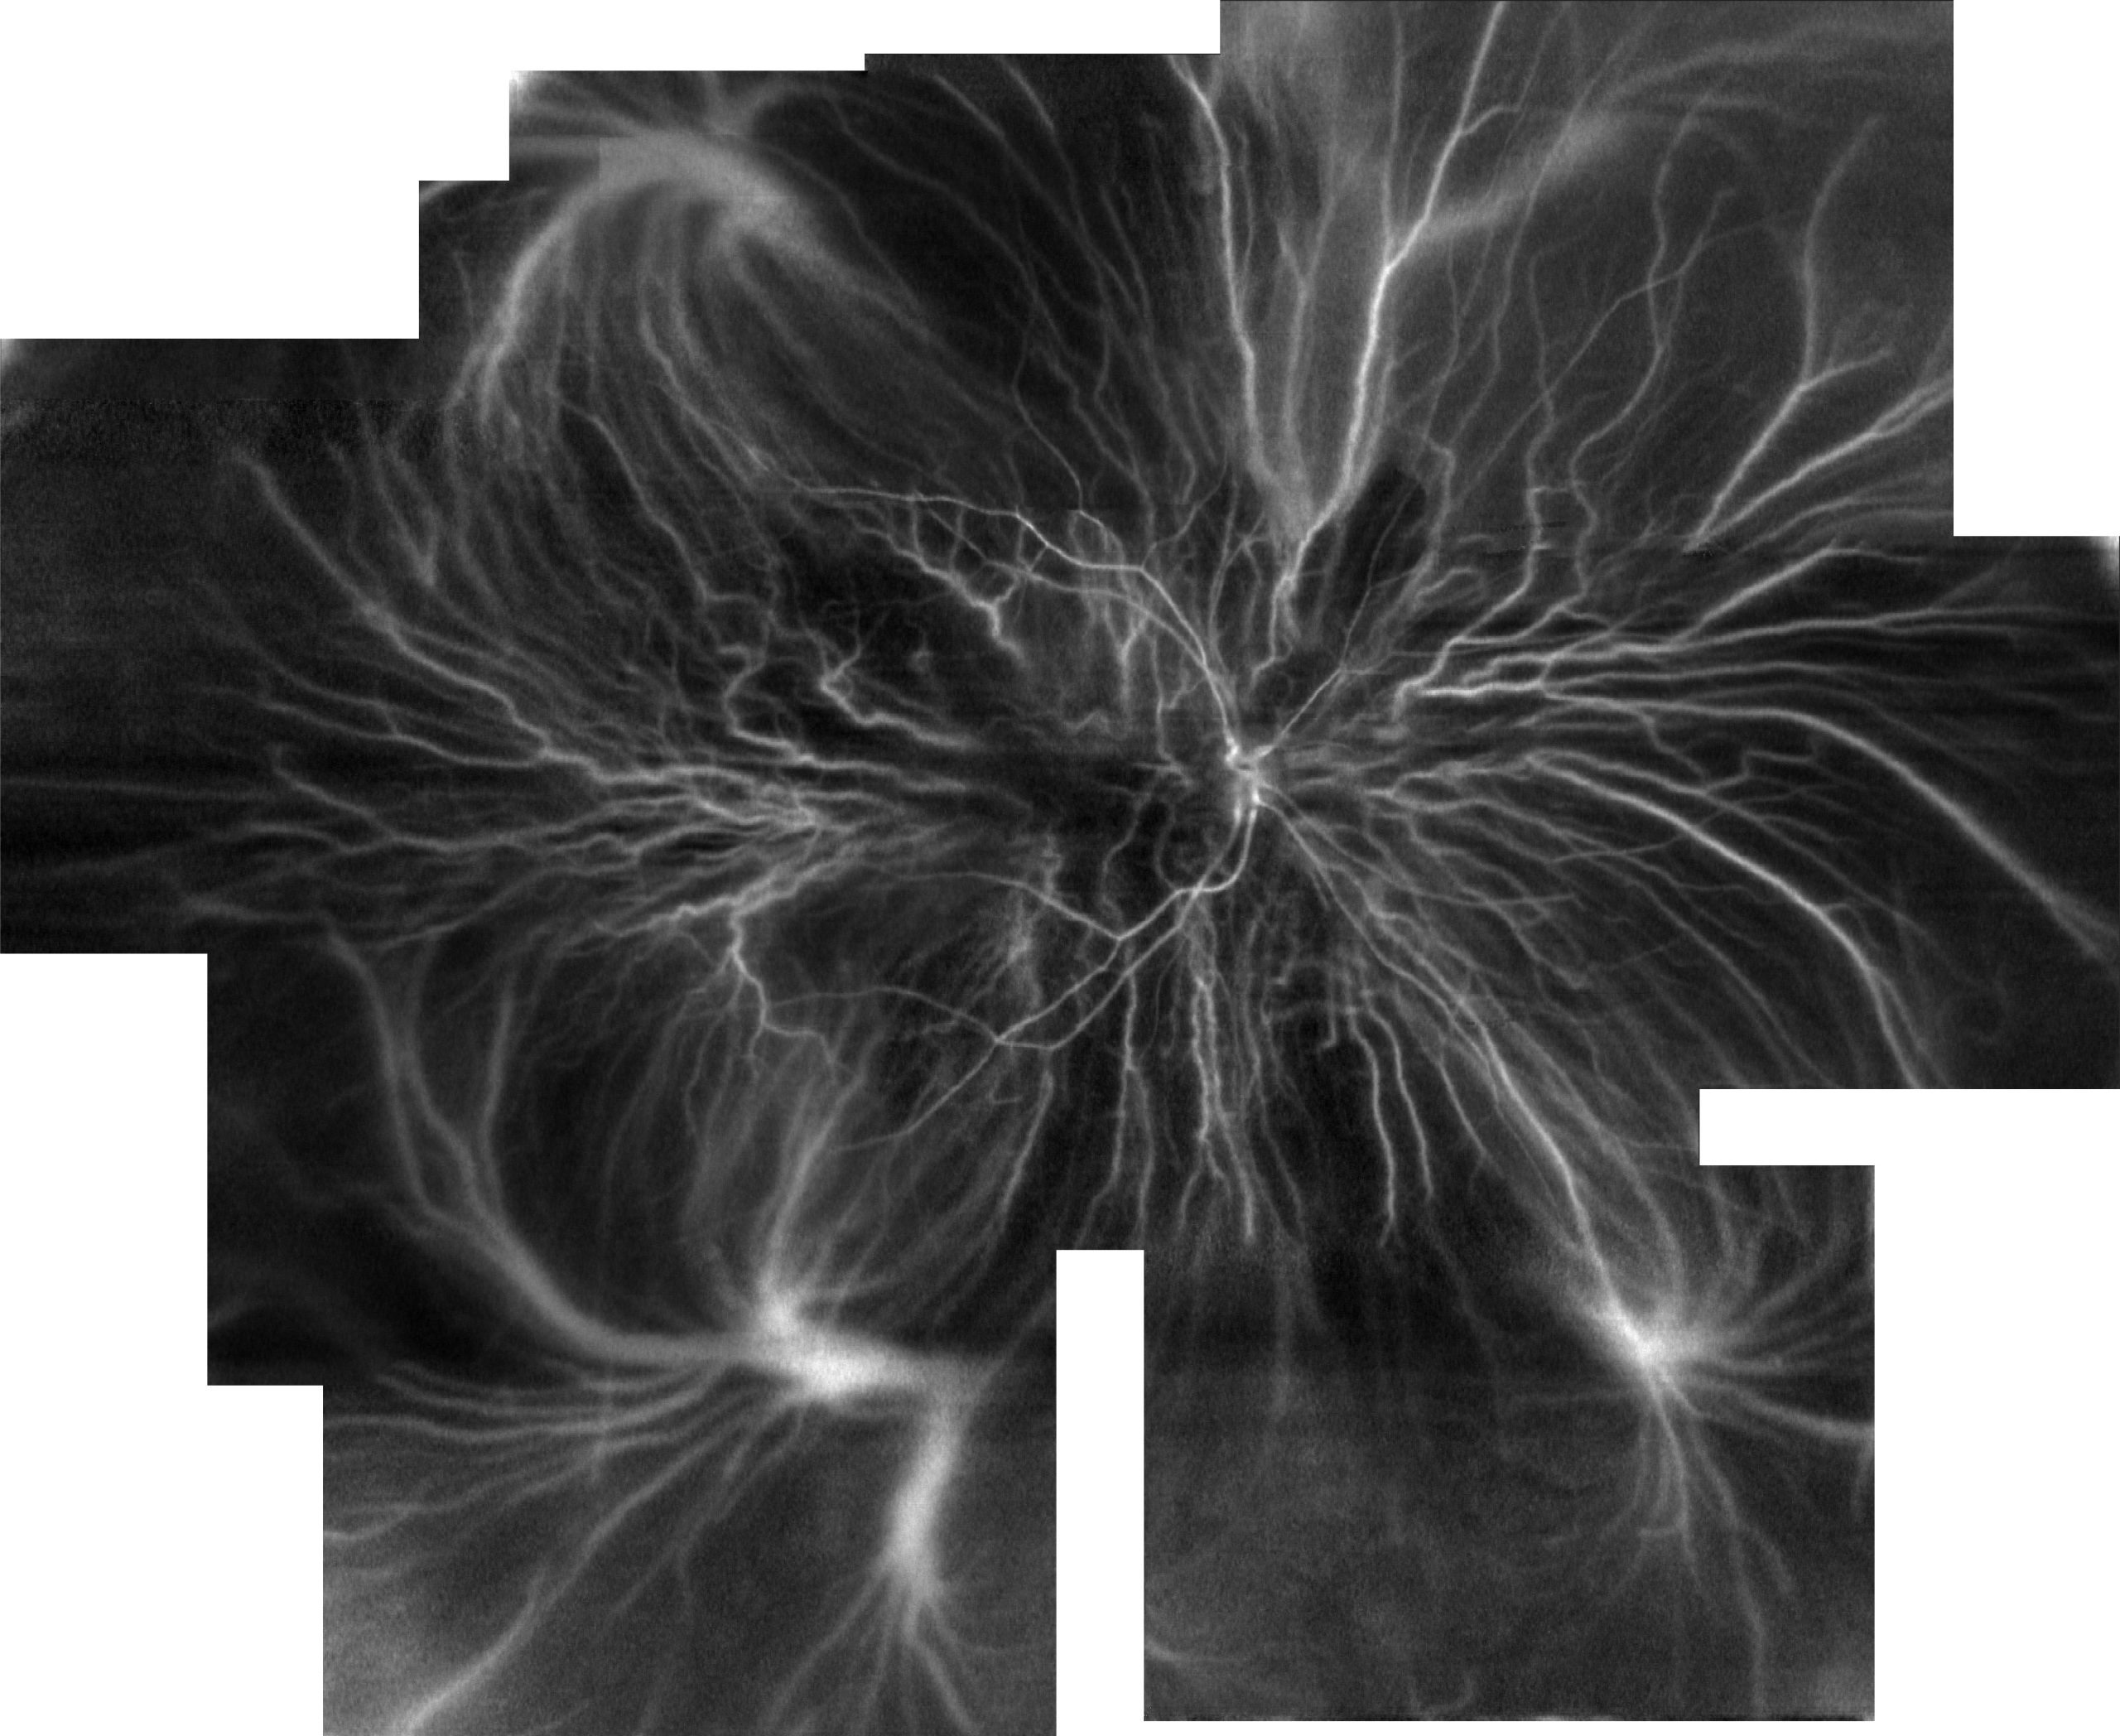

Ultra-wide mapping of retinal and choroidal vasculature with line-scanning Doppler flowmetry

“Visualizing the vasculature of the entire human eye posterior hemisphere without a contrast

agent”, Biomedical Optics Express, 10(1), 167-180, (2019)